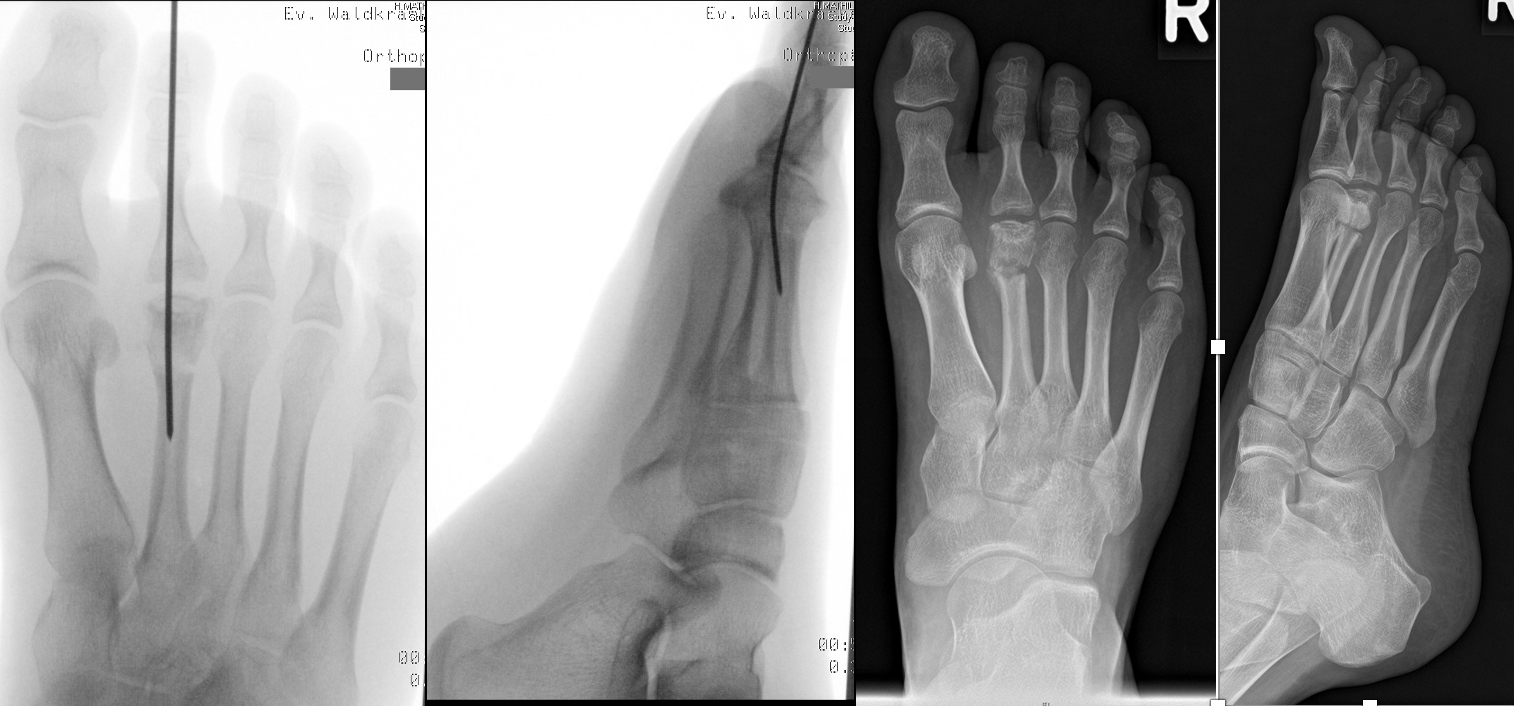

Abb. 2 a-c: offene Wachstumsfugen MT I Basis und Zehen (a), teilweise geöffnete Wachstumsfugen (b) und geschlossene Wachstumsfugen (c).

In der Regel bestehen aktive Wachstumsfugen bei Mädchen bis zum 12. und bei Jungen bis zum 14. Lebensjahr, mit Abweichungen von einem Jahr nach unten und nach oben. Präzise Informationen unter anderem darüber gibt das präoperative Röntgenbild (Abb. 2).

Die erforderlichen Osteotomien sind daher dem Fugenverlauf anzupassen, diese sind unbedingt zu respektieren. Wird eine Wachstumsfuge versehentlich mit der Fräse verletzt, kann durch partiellen oder kompletten Fugenverschluss ein Fehlwachstum provoziert werden. Achsabweichungen oder ein Wachstumstopp der betroffenen Region können die Folge sein. Offene Wachstumsfugen begrenzen die Osteotomieausrichtung besonders im Bereich des dorsalen Calcaneus, der Metatarsale I Basis und der IV. oder V. Zehe im End- und Mittelglied.

Zusätzlich schränken Wachstumsfugen die Wahl der Osteosynthese ein. Eine die Fuge kreuzende Osteosynthese ist ausschließlich mit Kirschner-Drähten möglich (Abb. 3).

Abb. 3 a-j: Beispiel einer Calcaneusverschiebeosteotomie mit offenen Wachstumsfugen und der entsprechenden Osteosynthese mit Kirschner Drähten. Lokalisation der Osteotomie (a), Lage der Fräse (b-d), Drahtlage mehrere Ansichten (e-h), Heilung der Osteotomie 4 Wochen postoperativ und Entfernung der Drähte (i-j).